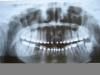

Dantukas Опубликовано 24 августа, 2011 Поделиться Опубликовано 24 августа, 2011 Здравствуйте!На завершающем этапе ортодонтического лечения, ортодонт порекомендовала установить имплант на место отсутствующей нижней 6ки (слева). Эта 6ка была удалена очень давно и травматично, потому кость в том месте истончилась. Консультировалась с несколькими врачами, которые занимаются имплантированием+протезированием и мне были предложены два довольно разных варианта:1. а) утолщение кости (искусственным материалом), курс антибиотиков, 4 мес. ждать;б) установка импланта, антибиотики, 4 мес. ждать;в) протезирование. 2. а) утолщение кости (искусственным материалом) и установка импланта за одну операцию, антибиотики, 4 мес. ждать;б) снятие брекетов и временный зуб пока сделают постоянный (2 недели);в) постоянный зуб накручивается на головку импланта. Второй вариант кажется привлекательнее, поскольку включает только 1 курс антибиотиков и только одну операцию, но возникает вопрос: можно ли за одну операцию и кость нарастить, и имплант поставить? Насколько широко это применяется на практике и оправдывается?Буду благодарна за комментарии, прилагаю панорамный снимок. Связь с темой Ссылка на комментарий

Dantukas Опубликовано 5 сентября, 2011 Автор Поделиться Опубликовано 5 сентября, 2011 возник ещё вопрос! Ортодонт, поглядев на панорамный снимок, сказала, что нужно лечить канал нижней 5ки, что около места имплантации. Объяснила, что там инфекция, которая может перекинуться в зону импланта, и имплант не приживётся. Но почему-то имплантолог во время консультации довольно равнодушно к той 5ке отнёсся. Как вы думаете, имеет ли смысл трогать эту 5ку (зуб не болит и никак не беспокоит, даже не был пломбирован) и, если трогать, то сколько нужно ждать после лечения канала 5ки до имплантации 6ки?спасибо. Ссылка на комментарий

Bier Опубликовано 6 сентября, 2011 Поделиться Опубликовано 6 сентября, 2011 в том и дело, что зуб целый - ни пломбы, ни дырки, красивый белый и никогда не беспокоил. Я так понимаю, если он живой, то лучше его не трогать, ведь если там под корнем какая инфекция - она будет ликвидирована курсом антибиотиков, который назначают после имплантации.. или я упрощаю?.. надо определить витальность зуба. Если он живой, под ним не может быть инфекции - это может быть просто разреженная кость из-за ортодонтических перемещений и все это само восстановится. Но картина по снимку заставляет задуматься, что зуб "умер" по каким-то причинам и там таки воспаление. Тогда надо вскрывать канал.Для определения витальности (живой/не живой) нужно провести либо холодовой тест, либо электро одонто метрию. Ссылка на комментарий